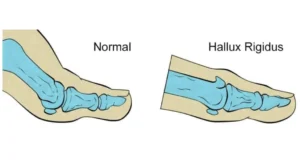

El Hallux Rigidus es una degeneración (artrosis) que afecta el cartílago de la articulación metatarsofalángica (MTF) del dedo gordo del pie. A diferencia del juanete, que es más frecuente en mujeres, esta el hallux rigidus predomina en hombres. Mientras que el hallux valgus implica una desviación del dedo gordo, el Hallux Rigidus se caracteriza por la rigidez en la movilidad y el dolor como consecuencia de un deterioro directo del cartílago articular. Como hemos señalado, el hallux rigidus es una artrosis en la articulación MTF.

La artrosis en la articulación conduce a la formación de crecimientos óseos patológicos (osteofitos dorsales), que generan irritación en la parte superior del dedo. Además, la inflamación y el deterioro articular suelen causar hinchazón en la zona afectada.